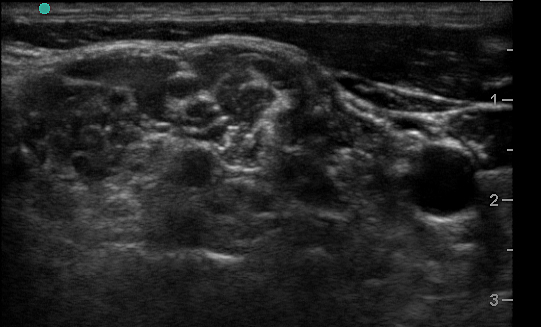

Figure 1. Transverse view over the sternocleidomastoid

Figure 2a. Transverse view through the interscalene space

Figure 2b. With labels

- Use a high-frequency 8-12 MHz linear probe and begin scanning transversely over the anterior neck at the level of the cricoid. (Figure 1)

- Probe indicator oriented to operator’s left.

- Depth should be set between 4-8 cm, depending on the size of the patient’s neck.

- Trachea should be clearly seen as a midline hyperechoic arc.

- Slide the probe laterally to the lateral border of the sternocleidomastoid (SCM) (Figure 1), which is a thin muscle superficial to the carotid and jugular.

- Move the probe inferiorly to identify the anterior scalene muscle deep to the lateral border of the SCM. (Figure 2)

- Triangular muscle that is thicker caudally

- Lateral to the internal jugular vein

- If not apparent, slide the probe in a cranio-caudal direction along the lateral border of the SCM to find it

- Identify the middle scalene muscle posterior to the anterior scalene muscle.

- The interscalene space is between these 2 scalene muscles and contains the brachial plexus

- Visualize the brachial plexus here as a stack of circles with hypoechoic centers

- The plexus will look more echogenic, bundled and honeycombed in the caudal interscalene space